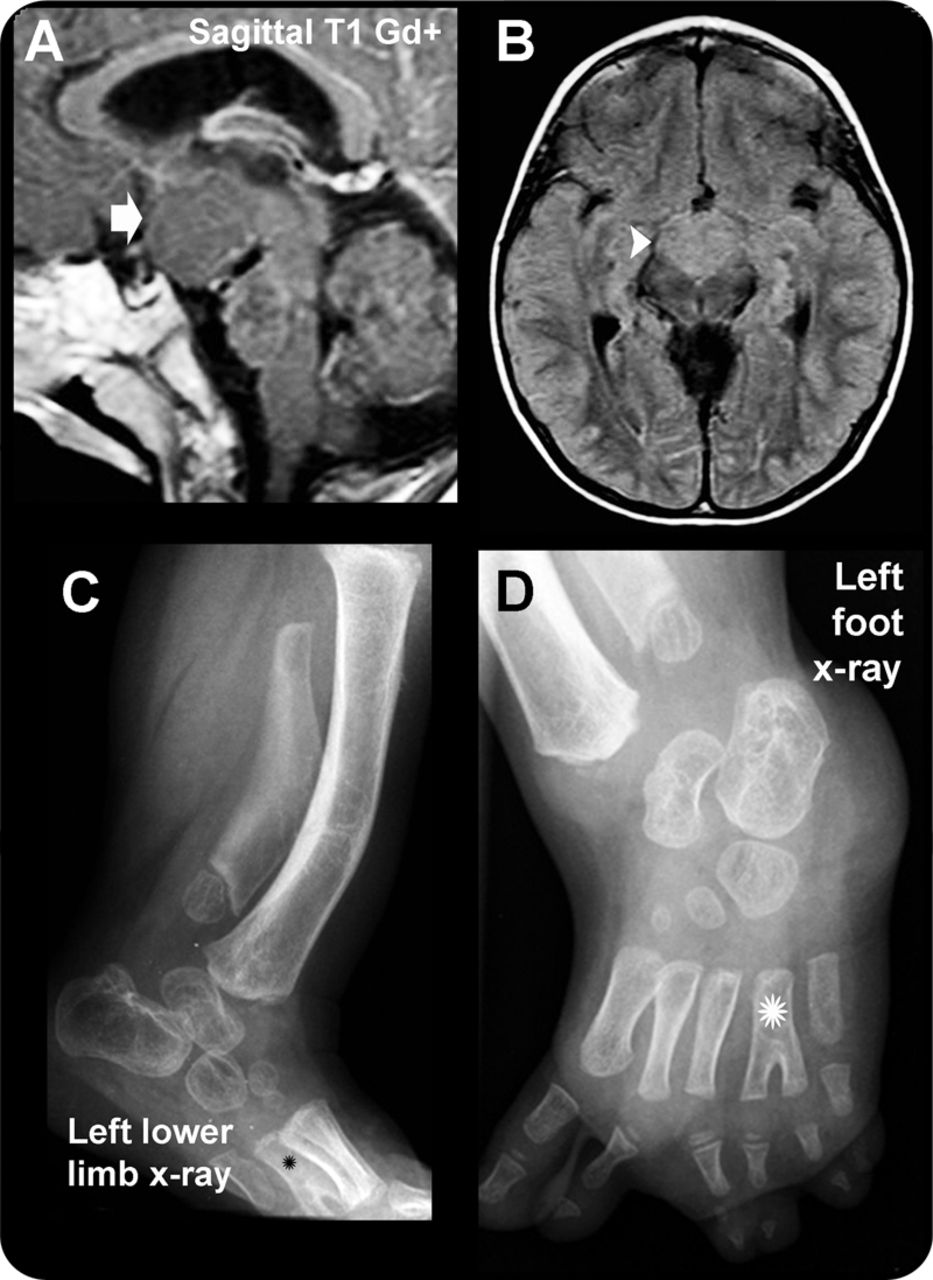

(A, B) MRI证实nonenhancing下丘脑错构瘤(箭头)isointense灰质在fluid-attenuated反转恢复(箭头)。(C, D)注意弯曲的长骨头,多指趾畸形、发育不良的跖骨(星号)。

孤立HH hyperintense在fluid-attenuated反转恢复并导致性早熟(PP)当他们面向向下(parahypothalamic病变),癫痫占主导地位在固着intrahypothalamic HH。2小灵通与isointense灰质HH,多指趾畸形,皮肤的并指,裂成两半的会厌,肛门闭锁,panhypopituitarism,激活造成移码突变(映射到染色体7 p13)作为一个常染色体显性遗传特点。1

所有的答案,我们收到了来自个人居民而非团体和他们都合理周到。三个被调查者正确识别的经典外观孤立下丘脑错构瘤(图1)和Pallister-Hall综合症(图2)。孤立时,下丘脑错构瘤呈现严重癫痫、更重要的神经功能障碍,更有可能与性早熟。Pallister-Hall综合症患者通常有控制癫痫发作和内分泌干扰性早熟。

教学这个神秘案件,尽管类似外观的MRI定位和T2 / fluid-attenuated反转恢复特征可能有助于区分这两个实体,因此成像可以作为临床预后因子的进化。